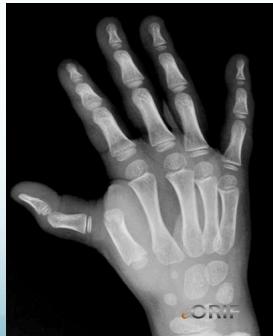

Fingers / Toes Dislocations

Common Causes:

• Sports, ball games, falls

Treatment:

• Reduction: Traction & counter traction

• Immobilization: Finger splint or buddy taping (with next finger/toe)